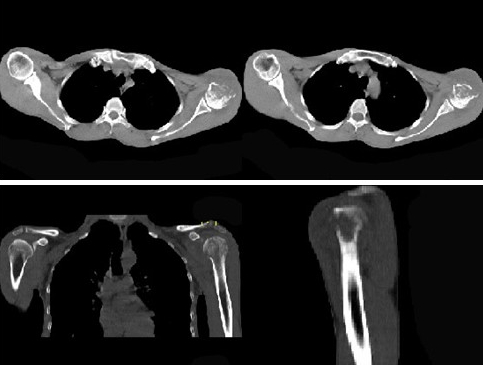

患者,男,29岁,行走时不慎跌倒,曾拟为左肱骨头骨骨折并行固定,但半年后疼痛未减轻,触压局部骨质松软,如触及乒乓球感,明显叩击痛,请结合提供图像,选择最佳答案()

A:化脓性骨髓炎

B:骨网状细胞肉瘤

C:左肱骨头骨折

D:骨转移瘤

E:骨结核